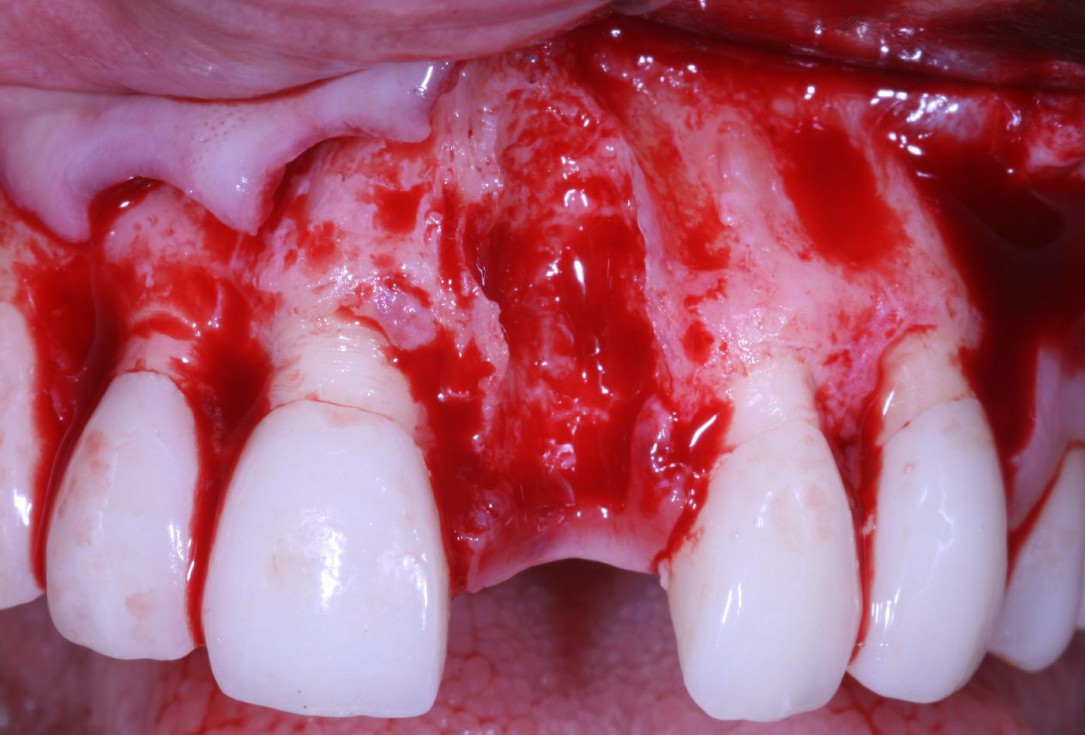

Lack of sufficient keratinized mucosa following extensive horizontal ridge augmentation